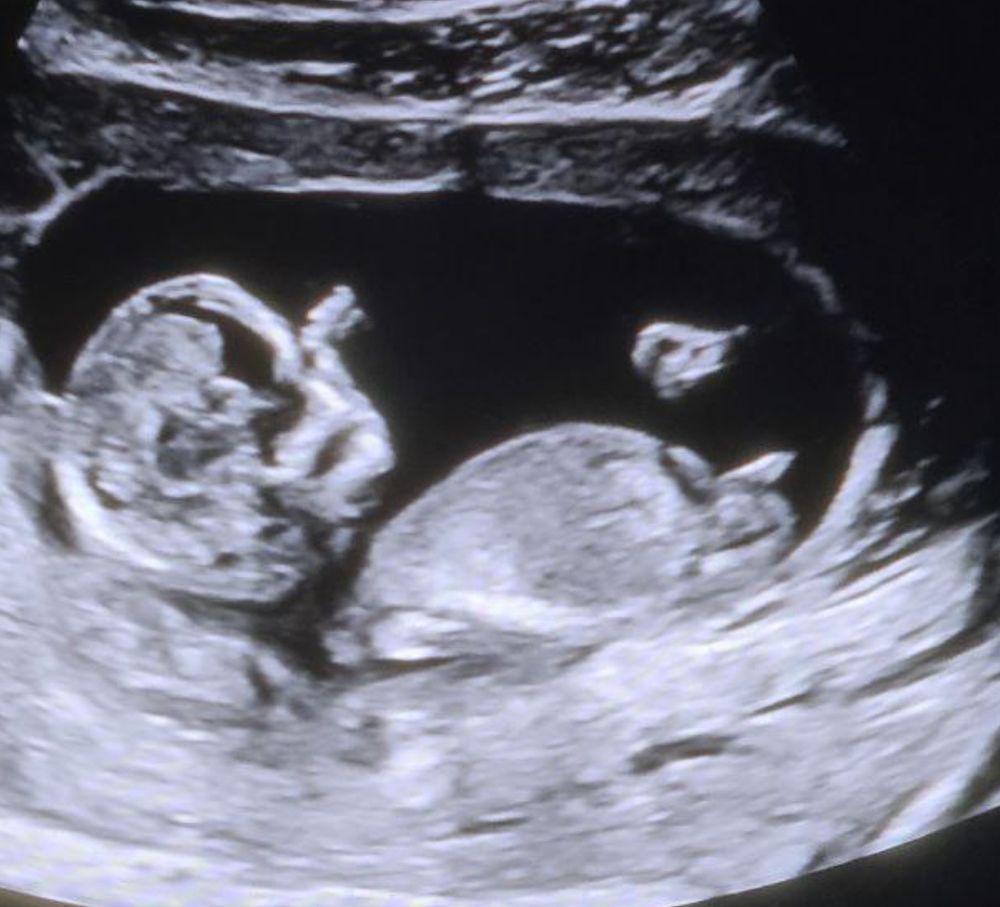

Половой бугорок 13 недель

Вижу, что параллельно позвоночнику, как у девочки, но мне кажется это мальчик)

Ия, я вот до узи начиталась про эти 30 градусов и паралельно позвоночнику и готовилась все сразу понять. Но лежа в кабинете, вижу то паралельно, то под углом (двигается карапуз), но такой бугорок явный, что мысли сразу про мальчика😅 и у врача такие же мысли. Но вот смотрю на фото и вижу: паралельно же!)

Вроде бы параллельно, но что то размерчик 🍆 как то смущает 😄 мне кажется мальчишка 🩵